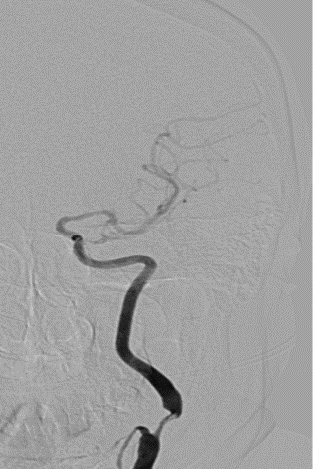

左侧颈内动脉起始段重度狭窄。

波科支架怎么样径技-弓上病例大赏|第205期·放疗后症状性颈动脉狭窄支架置入治疗一例_https://www.jmylbn.com_新闻资讯_第12张

波科支架怎么样径技-弓上病例大赏|第205期·放疗后症状性颈动脉狭窄支架置入治疗一例_https://www.jmylbn.com_新闻资讯_第13张

波科支架怎么样径技-弓上病例大赏|第205期·放疗后症状性颈动脉狭窄支架置入治疗一例_https://www.jmylbn.com_新闻资讯_第14张